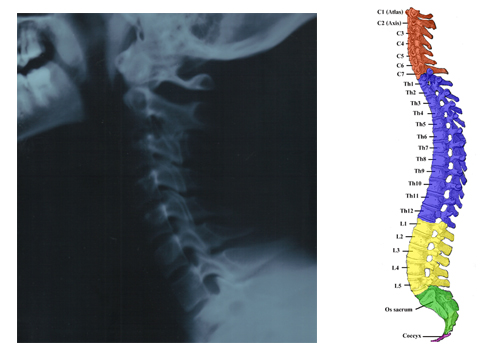

Stage 1: The human spine is not straight, but has as forward curve in the neck, a backward curve in the thoracic area, and a forward curve again in the lumbar area as seen in the illustration below.

In trauma the spinal curves will usually become distorted either by loss of normal primary curves as in the x-ray picture above, or with the development of scoliotic curves (sideways curves) as seen below.

Both of these distortions block normal motion and put unnatural stresses on the joints leading to inflammation. The loss of normal curves an the associated inflammation is the first stage of degeneration.